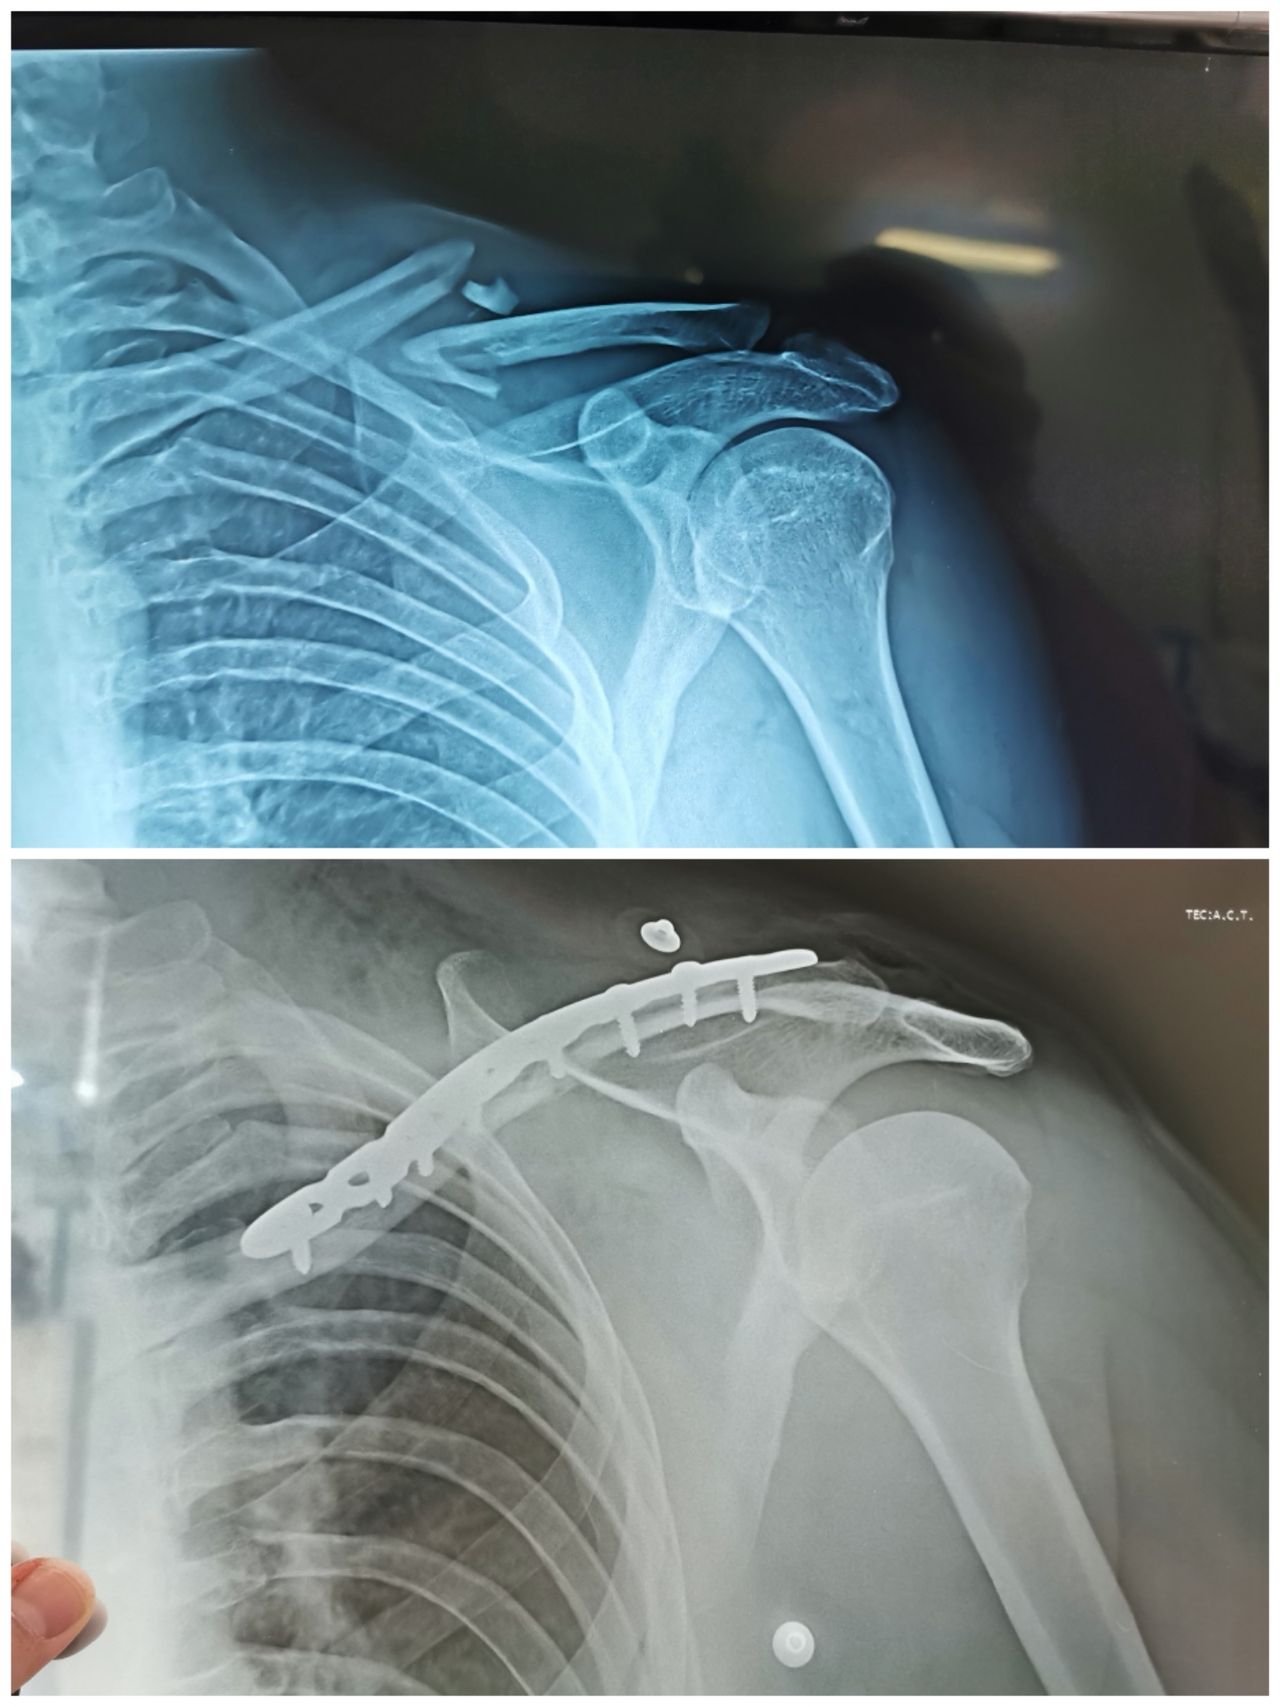

Fotos y videos